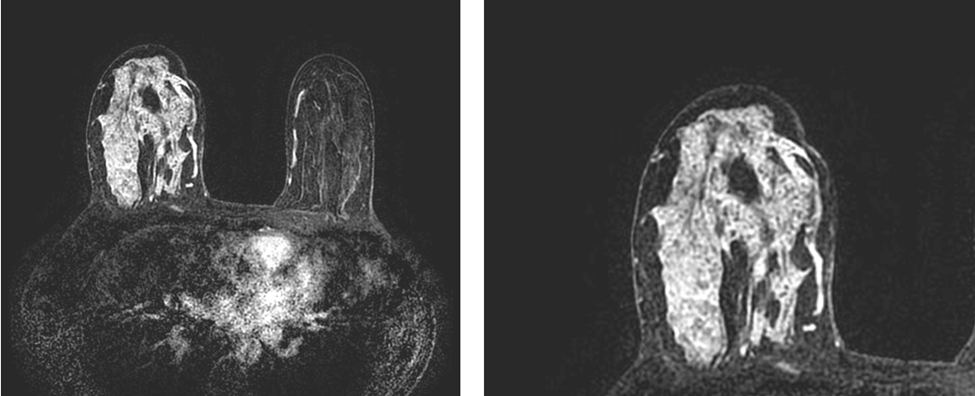

Pentru natura benignă pledează bilateralitatea, prezenta chistelor (micro/macrochiste pe secvențele T2), distribuția regională sau aspectul difuz. Trebuie menționat că aspectul difuz unilateral poate fi întâlnit și în carcinoamele difuze (caz în care, chiar dacă este vorba de un carcinom in situ, pacientele vor prezenta simptome clinice) sau la pacientele cu radioterapie în antecendente, la care în sânul iradiat este suprimată captarea de fond a parenchimului glandular (figura 4).

Fig. 4. Pacientă de 44 de ani care se prezintă pentru mastodinie unilaterală, neciclică și la care prin palpare se constată prezența de numeroase placarde indurate, nespecifice, localizate la nivelul tuturor cadranelor sânului drept. Mamografia nu pune în evidență leziuni patologice într-un sân extrem de dens (ACR 3) iar ecografic se vizualizeaza doar arii discrete de atenuare acustică dispersate la nivelul întregului sân. Examinarea RM pune în evidență o captare difuză de tip non-masă, asimetrică iar rezultatul histopatologic definitiv este de carcinom ductal in situ de tip non-comedo.